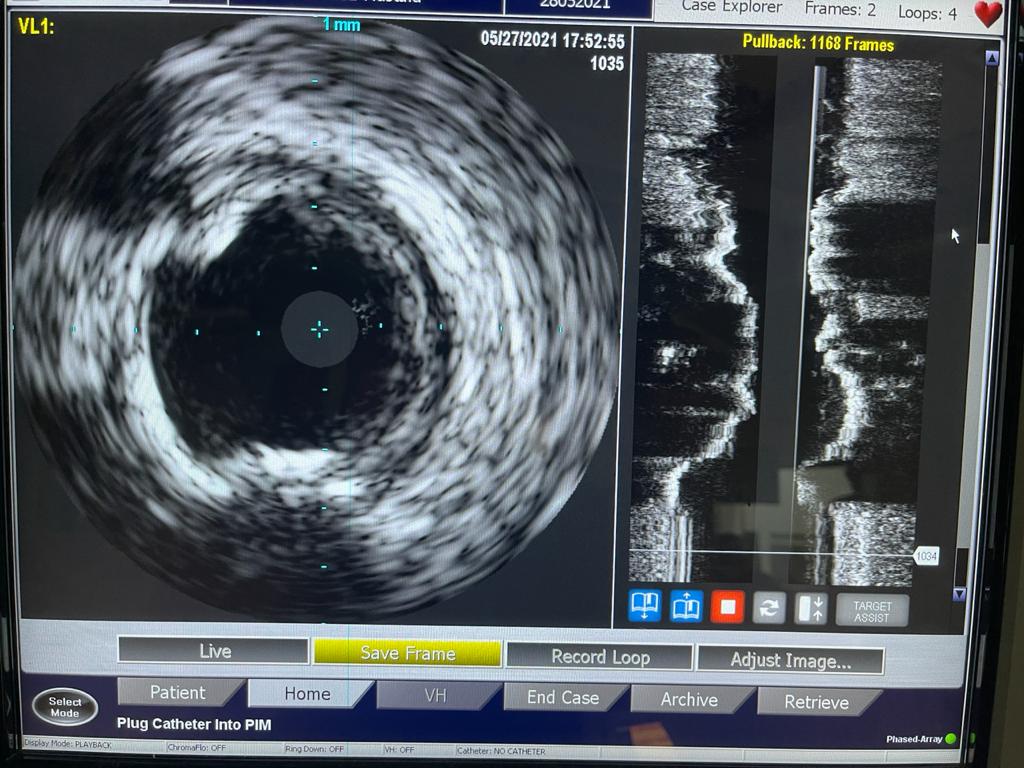

وأشارت الهيئة إلى أن الحالة الأولى من العمليات الدقيقة والمتطورة التي أجرتها مستشفى النصر التخصصي، كانت لمريض يبلغ من العمر 65 عامًا يعاني من ضيق شديد متكلس بالشريان التاجي الأيمن، بعد أن أجريت له جراحة قلب مفتوح منذ 15 سنة، وتم استخدام الشنيور الطبي لتوسيع الضيق، وتمت العملية بنجاح بالرغم من الصعوبة البالغة للحالة.

واستكملت أن الحالة الثالثة لمريضة تبلغ من العمر 70 عامًا، تعاني من قصور شديد بالشرايين التاجية للقلب وانسداد تام مزمن بالشريان التاجي الأيمن، إضافة إلى انسداد مزمن بالشريان التاجي الدائري الملنف وضيق شديد بالشريان الأمامي، ولها بنت مريضة من ذوي القدرات الخاصة، ولا تستطيع التغيب عنها لفترة طويلة، فتم علاجها على وجه السرعة عن طريق توسيع للشرايين بالبالونات العادية والدوائية إلى جانب تركيب دعامات دوائية لها باستخدام أحدث التقنيات العالمية بنجاح، واستطاعت الخروج من المستشفى في أقل من 24 ساعة لتعود إلى بيتها وابنتها التي تحتاج إلى رعايتها.

وتابعت الهيئة أنه قام بإجراء العمليات للمرضى الثلاثة في يوم واحد، فريق من أمهر الأطباء الأخصائيين والاستشاريين في علاج أمراض القلب والقساطر القلبية، يضم، الدكتور طارق رشيد أستاذ القلب والقسطرة وخبير حالات الانسداد المزمن للشرايين التاجية ورئيس قسم القسطرة القلبية بمستشفى النصر التخصصي، والدكتور ياسر صادق استشاري القلب وخبير القسطرة القلبية، الدكتور أمير البسطويسي استشاري جراحة القلب والصدر، الدكتور أحمد شبل استشاري القلب والقساطر التداخلية، الدكتور محمد علم الدين استشاري القلب والقسطرة العلاجية، الدكتور محمد لبيب استشاري جراحة الأوعية الدموية، وإخصائي علاج أمراض القلب والأوعية الدموية الدكتور معتز سلامة و الدكتور محمد عطا، أخصائي علاج أمراض القلب والقسطرة العلاجية الدكتور مصطفى رفعت، الدكتور أحمد عبد الرؤوف أخصائي التخدير بالمستشفى.

ومن جانبه أكد الدكتور طارق رشيد أن ما يحدث في قسم القلب بمستشفى النصر إنجاز يتفوق على النسب العالمية خاصة في مجال القساطر التداخلية، منوهًا أن الهيئة العامة للرعاية الصحية تعمل في الفترة الحالية على توثيق تلك الأرقام بصورة علمية بحثية على المستوى العالمي لتوضيح الإنجاز الكبير الذي يحدث في جراحات القلب بالهيئة.